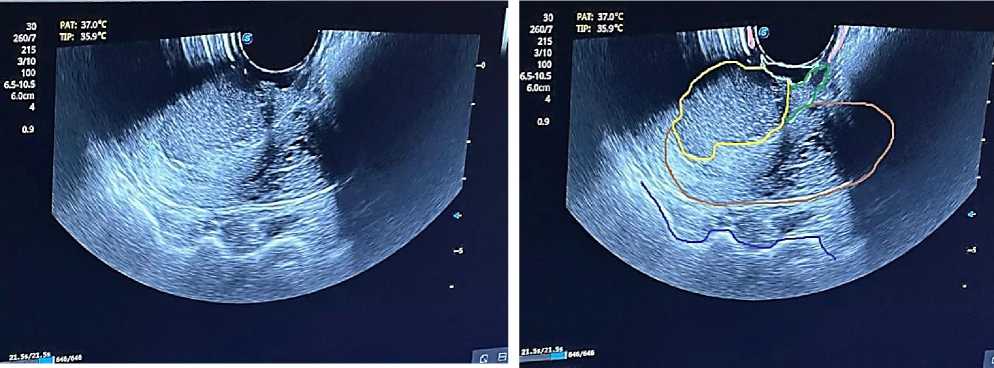

Рисунок 2. а) вагинальное исследование; б) ректальное исследование; в) ректо-вагинальное исследование

Рисунок 4. Трансректальное исследование: Розовая линия – влагалище; Красная линия – стенка мочевого пузыря; Бирюзовая линия – гематома влагалища; Зеленая линия – опухолевая инфильтрация верхней трети влагалища; Желтая линия – опухоль шейки матки; Фиолетовая линия – стенки кишечника